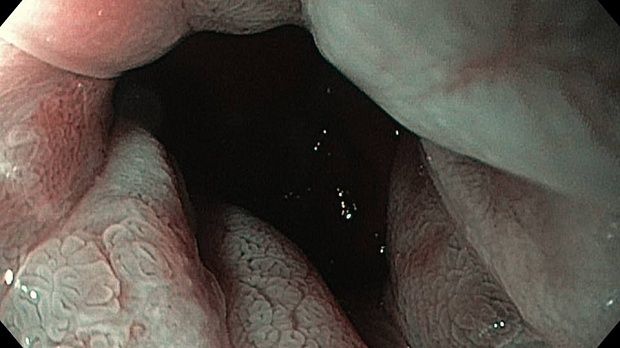

Публикации из социальных сетей: “Cobblestone esophagitis” (эзофагит со слизистой булыжной мостовой)

“Cobblestone esophagitis” (эзофагит со слизистой булыжной мостовой) - редкая эндоскопическая находка и ассоциируется с эозинофильным эзофагитом, кандидозом и пищеводом Барретта у взрослых. Он также может быть найден при тяжелом рефлюкс-эзофагите, вторичен к дистальной обструкции гастроинтестинального тракта. В нашем случае - это пациент после с 9-летним стажем бандажирования кардиального отдела желудка, признаками дуоденостаза, фундальной эрозивной гастропатией, расширением пищевода и уровнем жидкости в нем при горизонтальном положении, грыжи ПОД, эрозивно-язвенном дистальном эзофагите.. Пациент просто пришел удалить полип в прямой кишке и заодно посмотреть, что творится в желудке.... Ацетообеление+NBI+биопсия. ИПП на 3-4 мес и повтор для решения о Барретте.